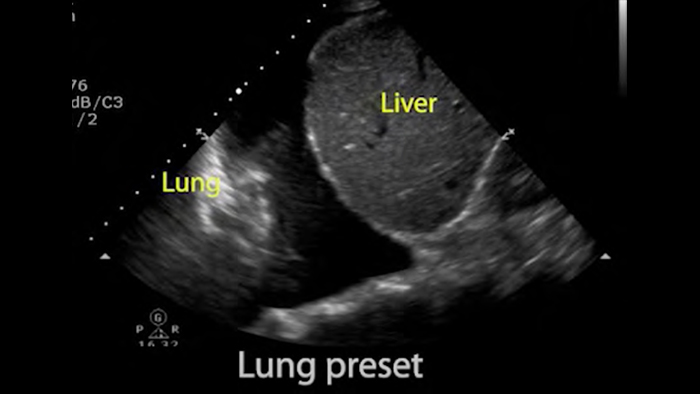

Use Lumify for airway and pulmonary assessment

Lumify POCUS solutions can help you detect the endotracheal tube within the trachea, assist in emergent cricothyrotomy procedures, diagnose pleural effusion and interstitial alveolar diseases.

Basics of lung ultrasound